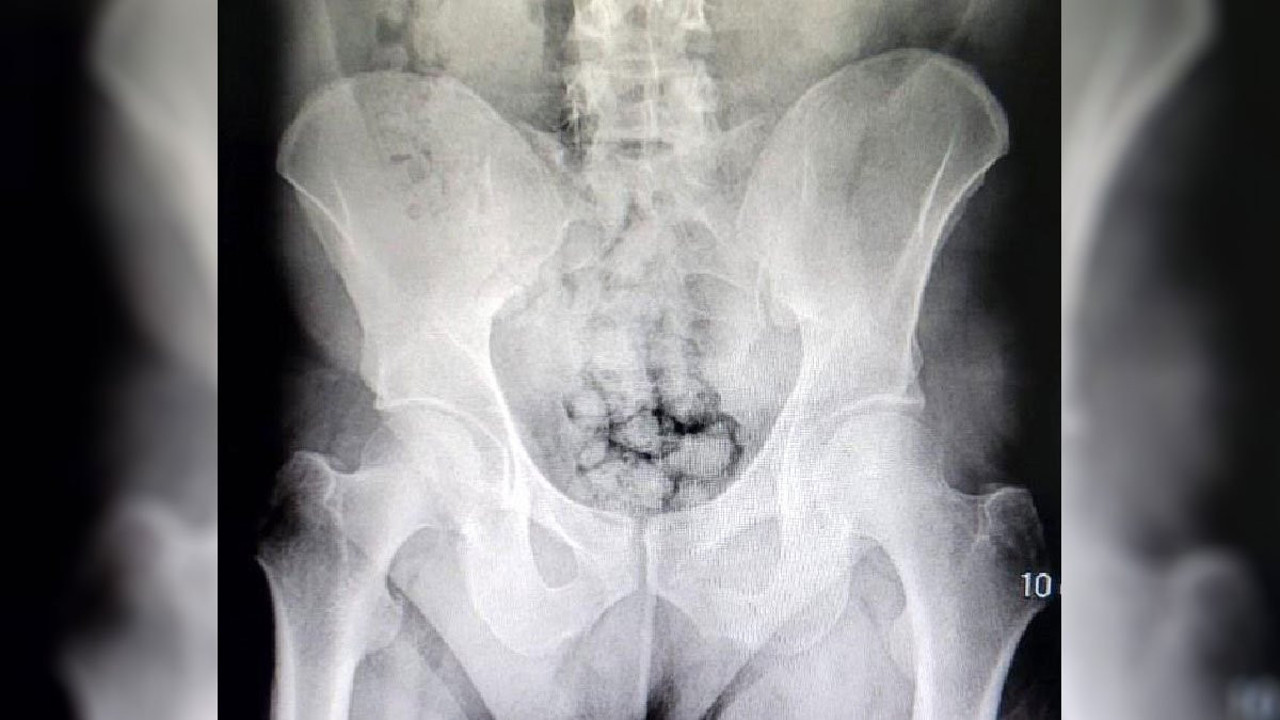

Hastanede yapılan röntgen incelemesinde, şahısların midesinde metamfetamin kapsülü olduğu ortaya çıktı.